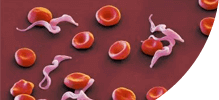

- Паразитларни фалаж қилади ва тухумларини 48 соат ичида йўқ қилади

- У танадан ажралиб, 2-3 ҳафта ичида танадан чиқариб ташланади